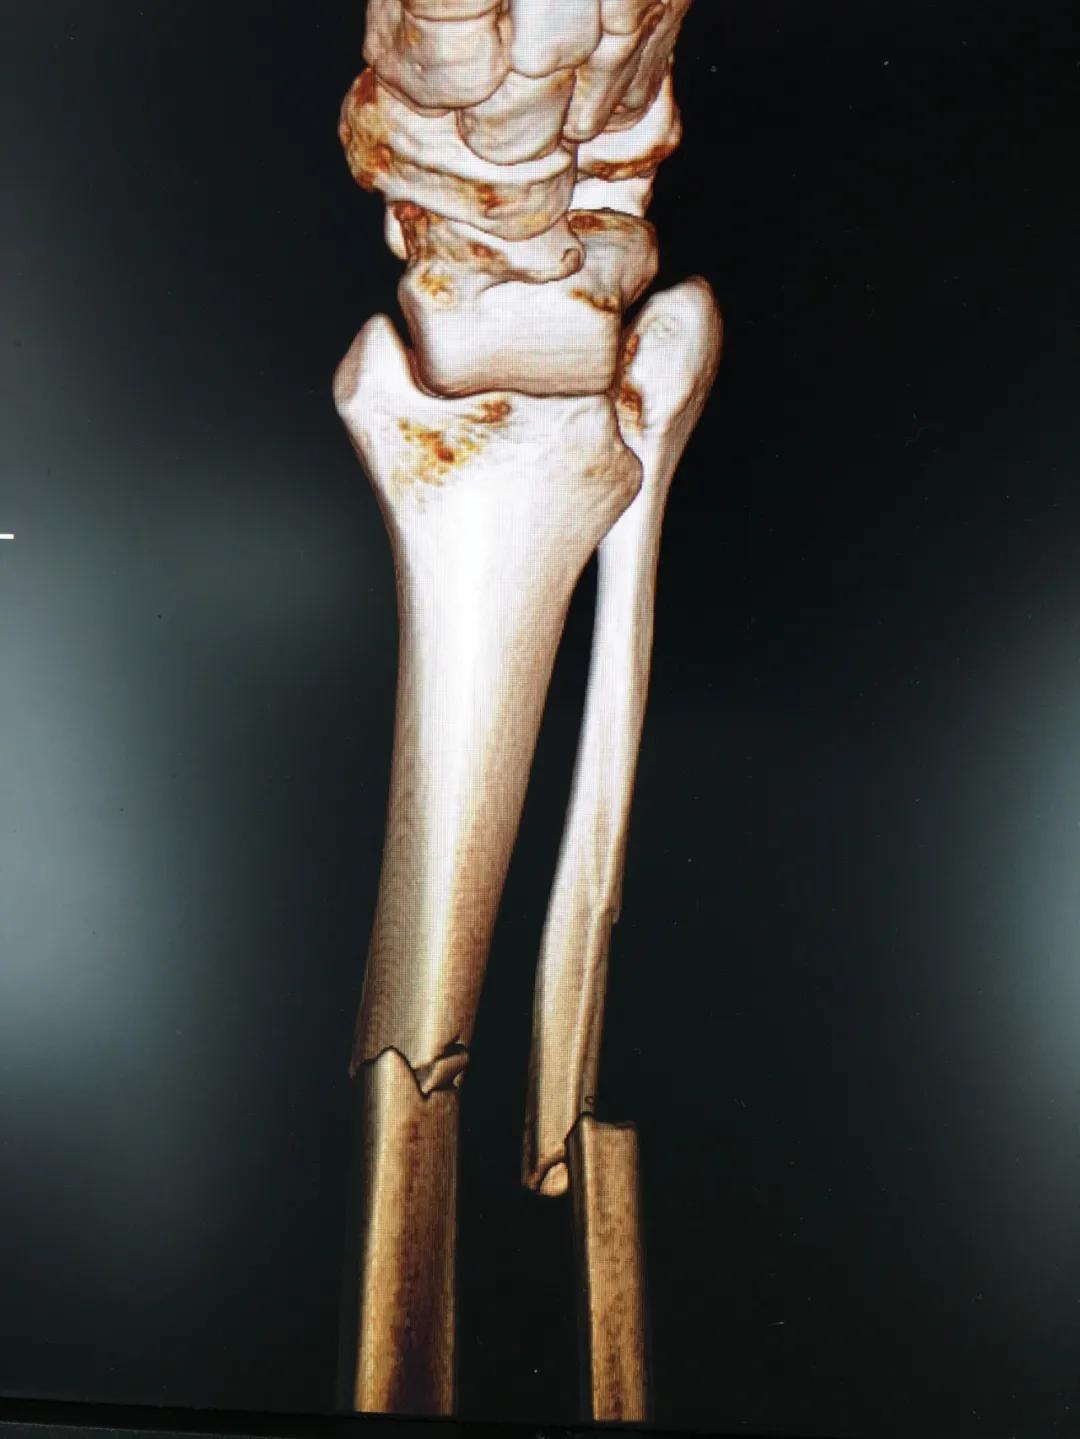

刘阿姨半个月前骑电动车时与小轿车相撞,导致了左胫腓骨粉碎性骨折,小腿骨碎成了三段。"然而,在术前丈夫周先生对刘阿姨的治疗却拿不定主意。“我妻子身上有多种基础疾病,患高血压15年,糖尿病也有8年多了。这里的诊疗技术,能不能保障手术的安全?手术前,我们家属的心中确实也很忐忑!"由于对我院创伤技术水平不太了解,周先生已经准备要转院治疗。

为患者实施的骨折微创复位固定技术是创伤骨科的特色技术。相较传统手术需要20公分的切口,微创手术只需要3公分左右。闭合复位髓内钉固定技术、经皮插板内固定技术(mippo技术)、闭合复位空心螺钉固定技术等一系列的微创复位固定技术,具有切口小、出血少、创伤小、愈合快、疤痕小等优点,骨折术后并发症明显降低,患者还可以早期负重功能锻炼。